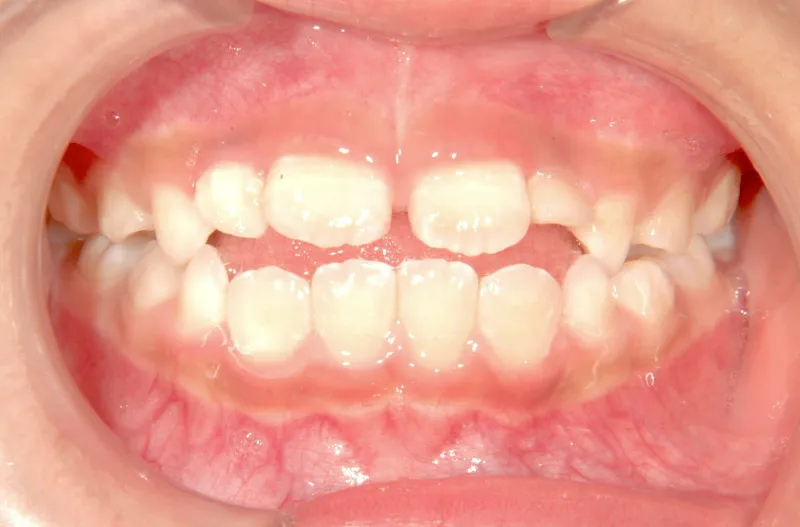

• 初診

初診時年齢 小学校1年生 (女性) 主訴 前歯で噛めない

診断名 叢生・開咬 装置名

状態 永久歯が生える隙間がない(叢生)

前歯で噛めない(開咬/オープンバイト)

舌の癖によって下の前歯が出て、上の前歯が短いです。

取り外し式の装置で上下の歯並びを拡げて、下の前歯を引っ込めます。

初診